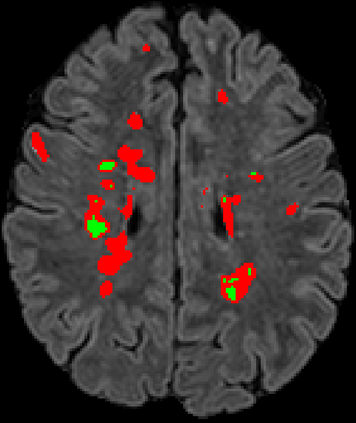

Recently, segmentation methods based on Convolutional Neural Networks (CNNs) showed promising performance in automatic Multiple Sclerosis (MS) lesions segmentation. These techniques have even outperformed human experts in controlled evaluation conditions such as Longitudinal MS Lesion Segmentation Challenge (ISBI Challenge). However state-of-the-art approaches trained to perform well on highly-controlled datasets fail to generalize on clinical data from unseen datasets. Instead of proposing another improvement of the segmentation accuracy, we propose a novel method robust to domain shift and performing well on unseen datasets, called DeepLesionBrain (DLB). This generalization property results from three main contributions. First, DLB is based on a large group of compact 3D CNNs. This spatially distributed strategy ensures a robust prediction despite the risk of generalization failure of some individual networks. Second, DLB includes a new image quality data augmentation to reduce dependency to training data specificity (e.g., acquisition protocol). Finally, to learn a more generalizable representation of MS lesions, we propose a hierarchical specialization learning (HSL). HSL is performed by pre-training a generic network over the whole brain, before using its weights as initialization to locally specialized networks. By this end, DLB learns both generic features extracted at global image level and specific features extracted at local image level. DLB generalization was validated in cross-dataset experiments on MSSEG'16, ISBI challenge, and in-house datasets. During experiments, DLB showed higher segmentation accuracy, better segmentation consistency and greater generalization performance compared to state-of-the-art methods. Therefore, DLB offers a robust framework well-suited for clinical practice.